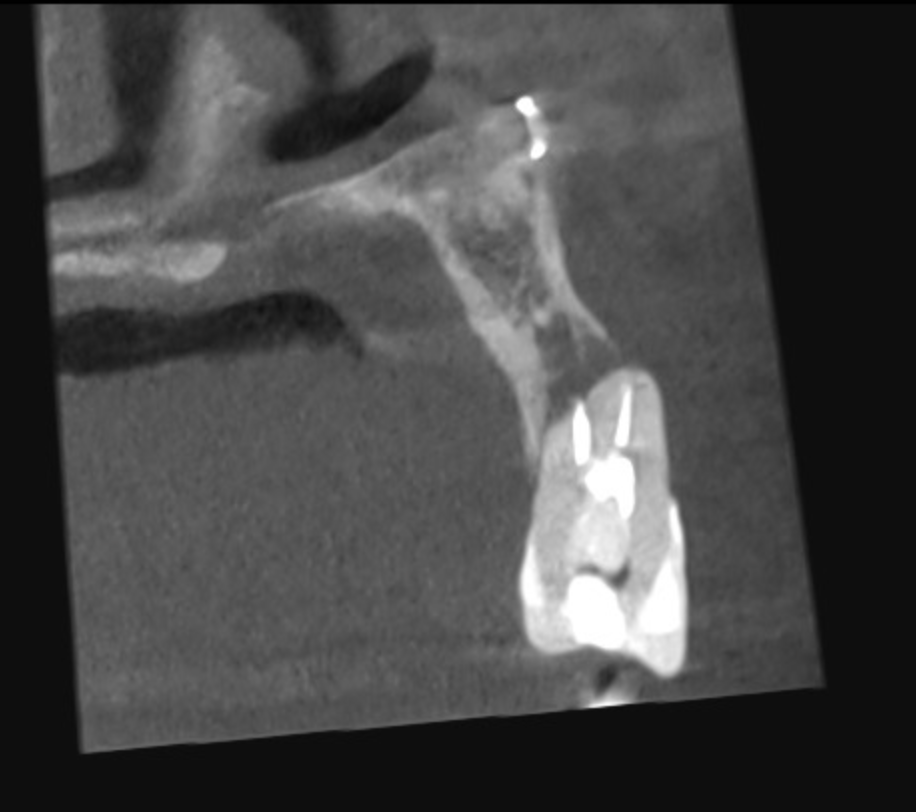

Vertical root fracture